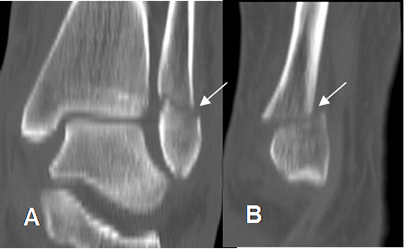

Fig 43. Fracturas del meléolo externo.

A: TAC reconstrucción coronal y B: TAC reconstrucción sagital. Fractura en sentido transverso del maleolo externo, levemente desplazada.